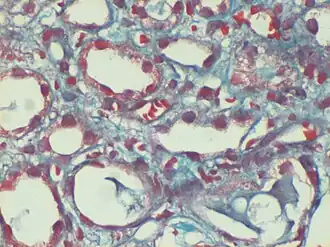

Capilares sanguíneos en los que se pueden observar eritrocitos falciformes.

La anemia de células falciformes, además, tiene un componente relacionado con la raza muy importante, ya que es la enfermedad genética más frecuente entre la población negra. Se trata de una enfermedad recesiva bastante cruel ya que los que la sufren no pueden realizar esfuerzos, ya que corren un grave riesgo de sufrir una insuficiencia respiratoria aguda que les ocasione repentinamente la muerte. Pues bien, la discriminación genética aparece cuando el gobierno realizó un estudio poblacional para detectar individuos que portaran este gen. La anemia de células falciformes no tiene cura y por tanto, si alguien era diagnosticado de anemia de células falciformes no poseía la más mínima esperanza de curación. El problema se hizo patente cuando el gobierno declaró obligatorio en varios estados realizar la prueba de detección a los recién nacidos y a los escolares, sin seguir un programa paralelo de orientación genética que pudiera ofrecer consejo a las familias afectadas, y cuando el público comenzó a confundir a las personas portadoras (heterocigóticas) con las enfermas, debido a la completa falta de una campaña informativa. Por si esto fuera poco, Linus Pauling, que había descubierto el método de análisis de la hemoglobina, realizó unas desafortunadas declaraciones en las que sugería que se marcara de alguna manera a los portadores para que no se mezclaran y no tuvieran hijos entre sí. La información que se recogió en este estudio pasó a formar parte del historial médico de los niños que estaban afectados. Las compañías de seguros comenzaron entonces a negarse a formalizar el seguro si conocían que su posible cliente padecía anemia de células falciformes, e incluso si era simplemente portador del gen. También el mercado de trabajo comenzó a discriminar a los enfermos y portadores. A las personas de color que portaban el gen se les negaba por ejemplo el trabajo en compañías aéreas porque se pensaba que su sangre reaccionaría mal al encontrarse a bajas presiones causados por la altura del avión (algo que es erróneo).